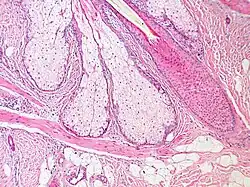

Histologisches Bild einer Haarwurzel mit Talgdrüsen und Haaraufrichtemuskel

Die Musculi arrectores pilorum (Singular: Musculus arrector pili) (Haaraufrichtemuskel, Haarbalgmuskel oder Pilomotor) sind kleine, aus glatter Muskulatur bestehende Muskeln, die am äußeren Rand der Haare mit Ausnahme der Primärhaare (Deck- und Fellhaare) ansetzen. Sie entspringen der oberflächlichen Schicht der Lederhaut und setzen unterhalb der Talgdrüse am Haar an. Die Innervation erfolgt unwillkürlich durch sympathische Nervenfasern.